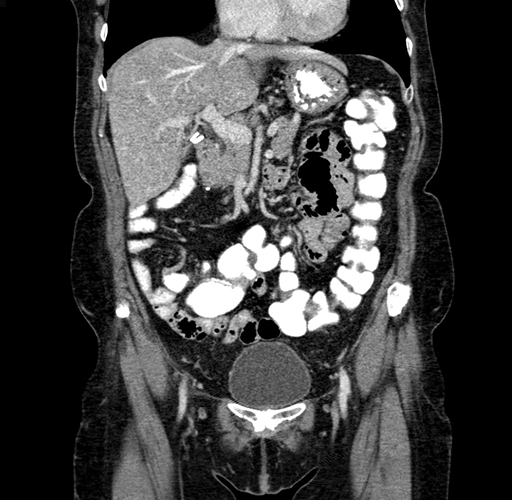

Pre-Chemo: Coronal Venous